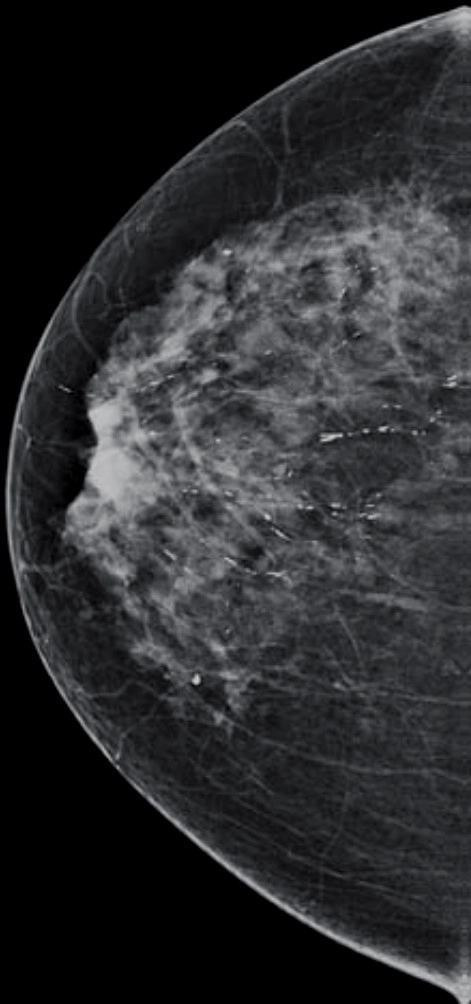

Vôi hóa tuyến vú (Breast calcifications)

Vôi hóa lành tính

Vôi hóa nghi ngờ

Vôi hóa nghi ngờ ác tính ở vú (Suspicious breast calcifications)